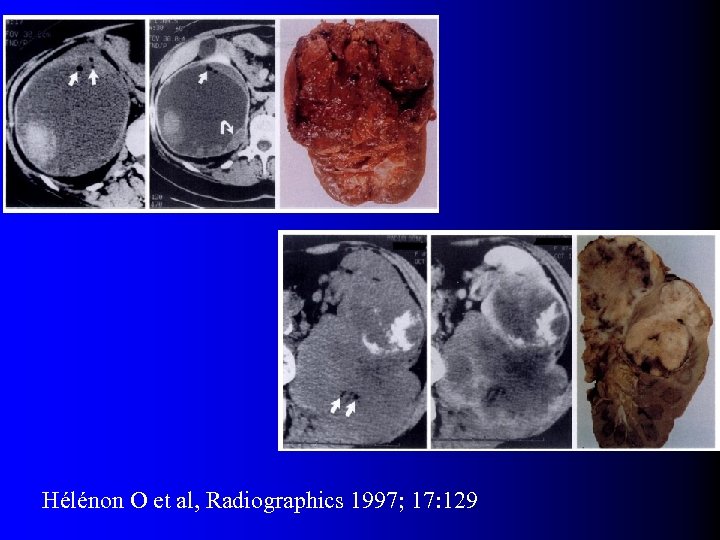

Tumeurs malignes à contenu graisseux l OUI… presque l Quelques rares exceptions dans la littérature – Incorporation de graisse péri-rénale ou sinusale dans une volumineuse tumeur – Métaplasie osseuse avec éléments graisseux de moelle osseuse – Nécrose cholestérolique intra-tumorale (1) Hélénon O et al, Radiographics 1997; 17: 129 (2) Henderson RJ et al, J Urol 1997; 157: 1347 (3) Roy C et al, Br J Urol 1998; 71: 977 (4) Schuster TG et al, AJR 2004; 183: 1402

Tumeurs malignes à contenu graisseux l OUI… presque l Quelques rares exceptions dans la littérature – Incorporation de graisse péri-rénale ou sinusale dans une volumineuse tumeur – Métaplasie osseuse avec éléments graisseux de moelle osseuse – Nécrose cholestérolique intra-tumorale (1) Hélénon O et al, Radiographics 1997; 17: 129 (2) Henderson RJ et al, J Urol 1997; 157: 1347 (3) Roy C et al, Br J Urol 1998; 71: 977 (4) Schuster TG et al, AJR 2004; 183: 1402

Tumeurs malignes à contenu graisseux l Eléments diagnostiques: – Calcifications +++ – Large nécrose intra-tumorale avec petits foyers graisseux – Association avec ADP et thrombus tumoral non graisseux l D'une manière générale, se méfier d'un "AML" à croissance rapide…

Tumeurs malignes à contenu graisseux l Eléments diagnostiques: – Calcifications +++ – Large nécrose intra-tumorale avec petits foyers graisseux – Association avec ADP et thrombus tumoral non graisseux l D'une manière générale, se méfier d'un "AML" à croissance rapide…

Hélénon O et al, Radiographics 1997; 17: 129

Hélénon O et al, Radiographics 1997; 17: 129